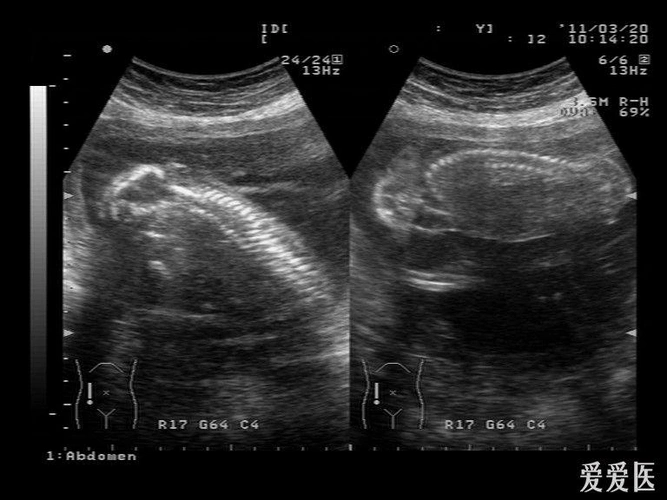

无脑儿 - 超声医学讨论版 - 爱爱医医学论坛

联体无脑儿 - 超声医学讨论版 - 爱爱医医学论坛

胎儿无脑畸形 - 超声医学讨论版 - 爱爱医医学论坛

【讨论】【原创】 无脑儿?露脑畸形?(已引产)